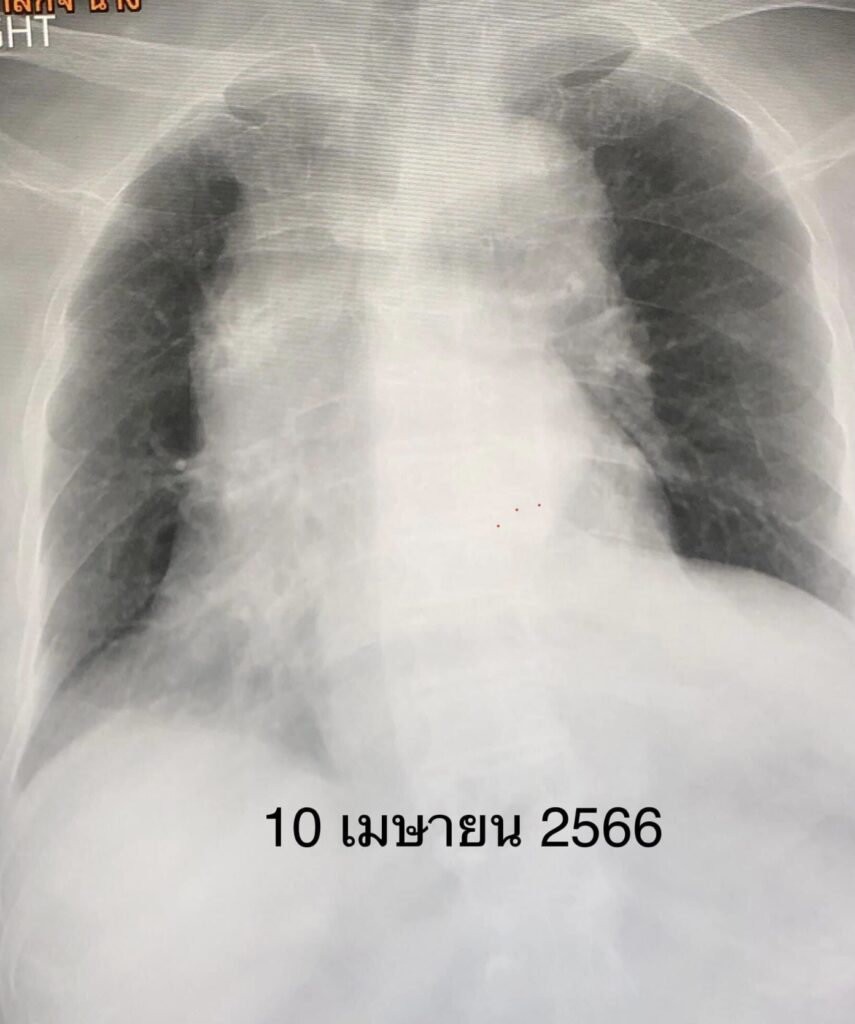

เริ่มไอ 2 วัน เหนื่อยเล็กน้อย ไม่มีไข้ ไม่เจ็บคอ ไม่มีน้ำมูก ตรวจ ATK บวก ติดเชื้อไวรัสโควิดครั้งแรกจากคนเฝ้าและลูกสาวที่อยู่ในบ้านเดียวกัน ผู้ป่วยรู้ตัวดี พูดได้ ไม่มีไข้ เอกซเรย์ปอดปกติ (ดูรูป) รับเข้านอนในโรงพยาบาลวันที่ 10 เมษายน 2566 เริ่มยาต้านไวรัสเรมเดซิเวียร์ฉีดเข้าเส้นเลือด

คืนที่เข้านอนในโรงพยาบาล เหนื่อยมากขึ้น เอกซเรย์ปอดพบปอดขวาทั้งข้างขาว (ดูรูป) เชื้อไวรัสโควิด-19 ทำให้เสมหะข้นเหนียวจนอุดหลอดลม ปอดขวาทั้งข้างแฟบ ต้องใส่ท่อหายใจและเครื่องช่วยหายใจ